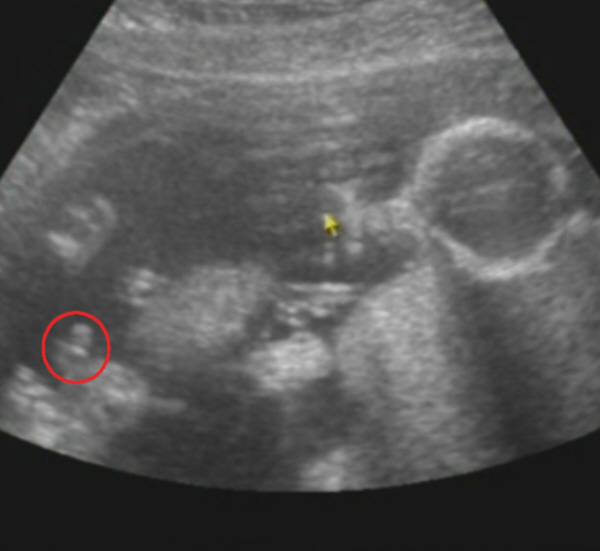

Végre sikerült bescannelnem a múltkori 2D-s UH képet.

Kép

Látszik szemből a pofija...az egyik kezecskéje a mellkasa mellett, míg a másikkal fogja a fülét, és látszik a könyöke. :)